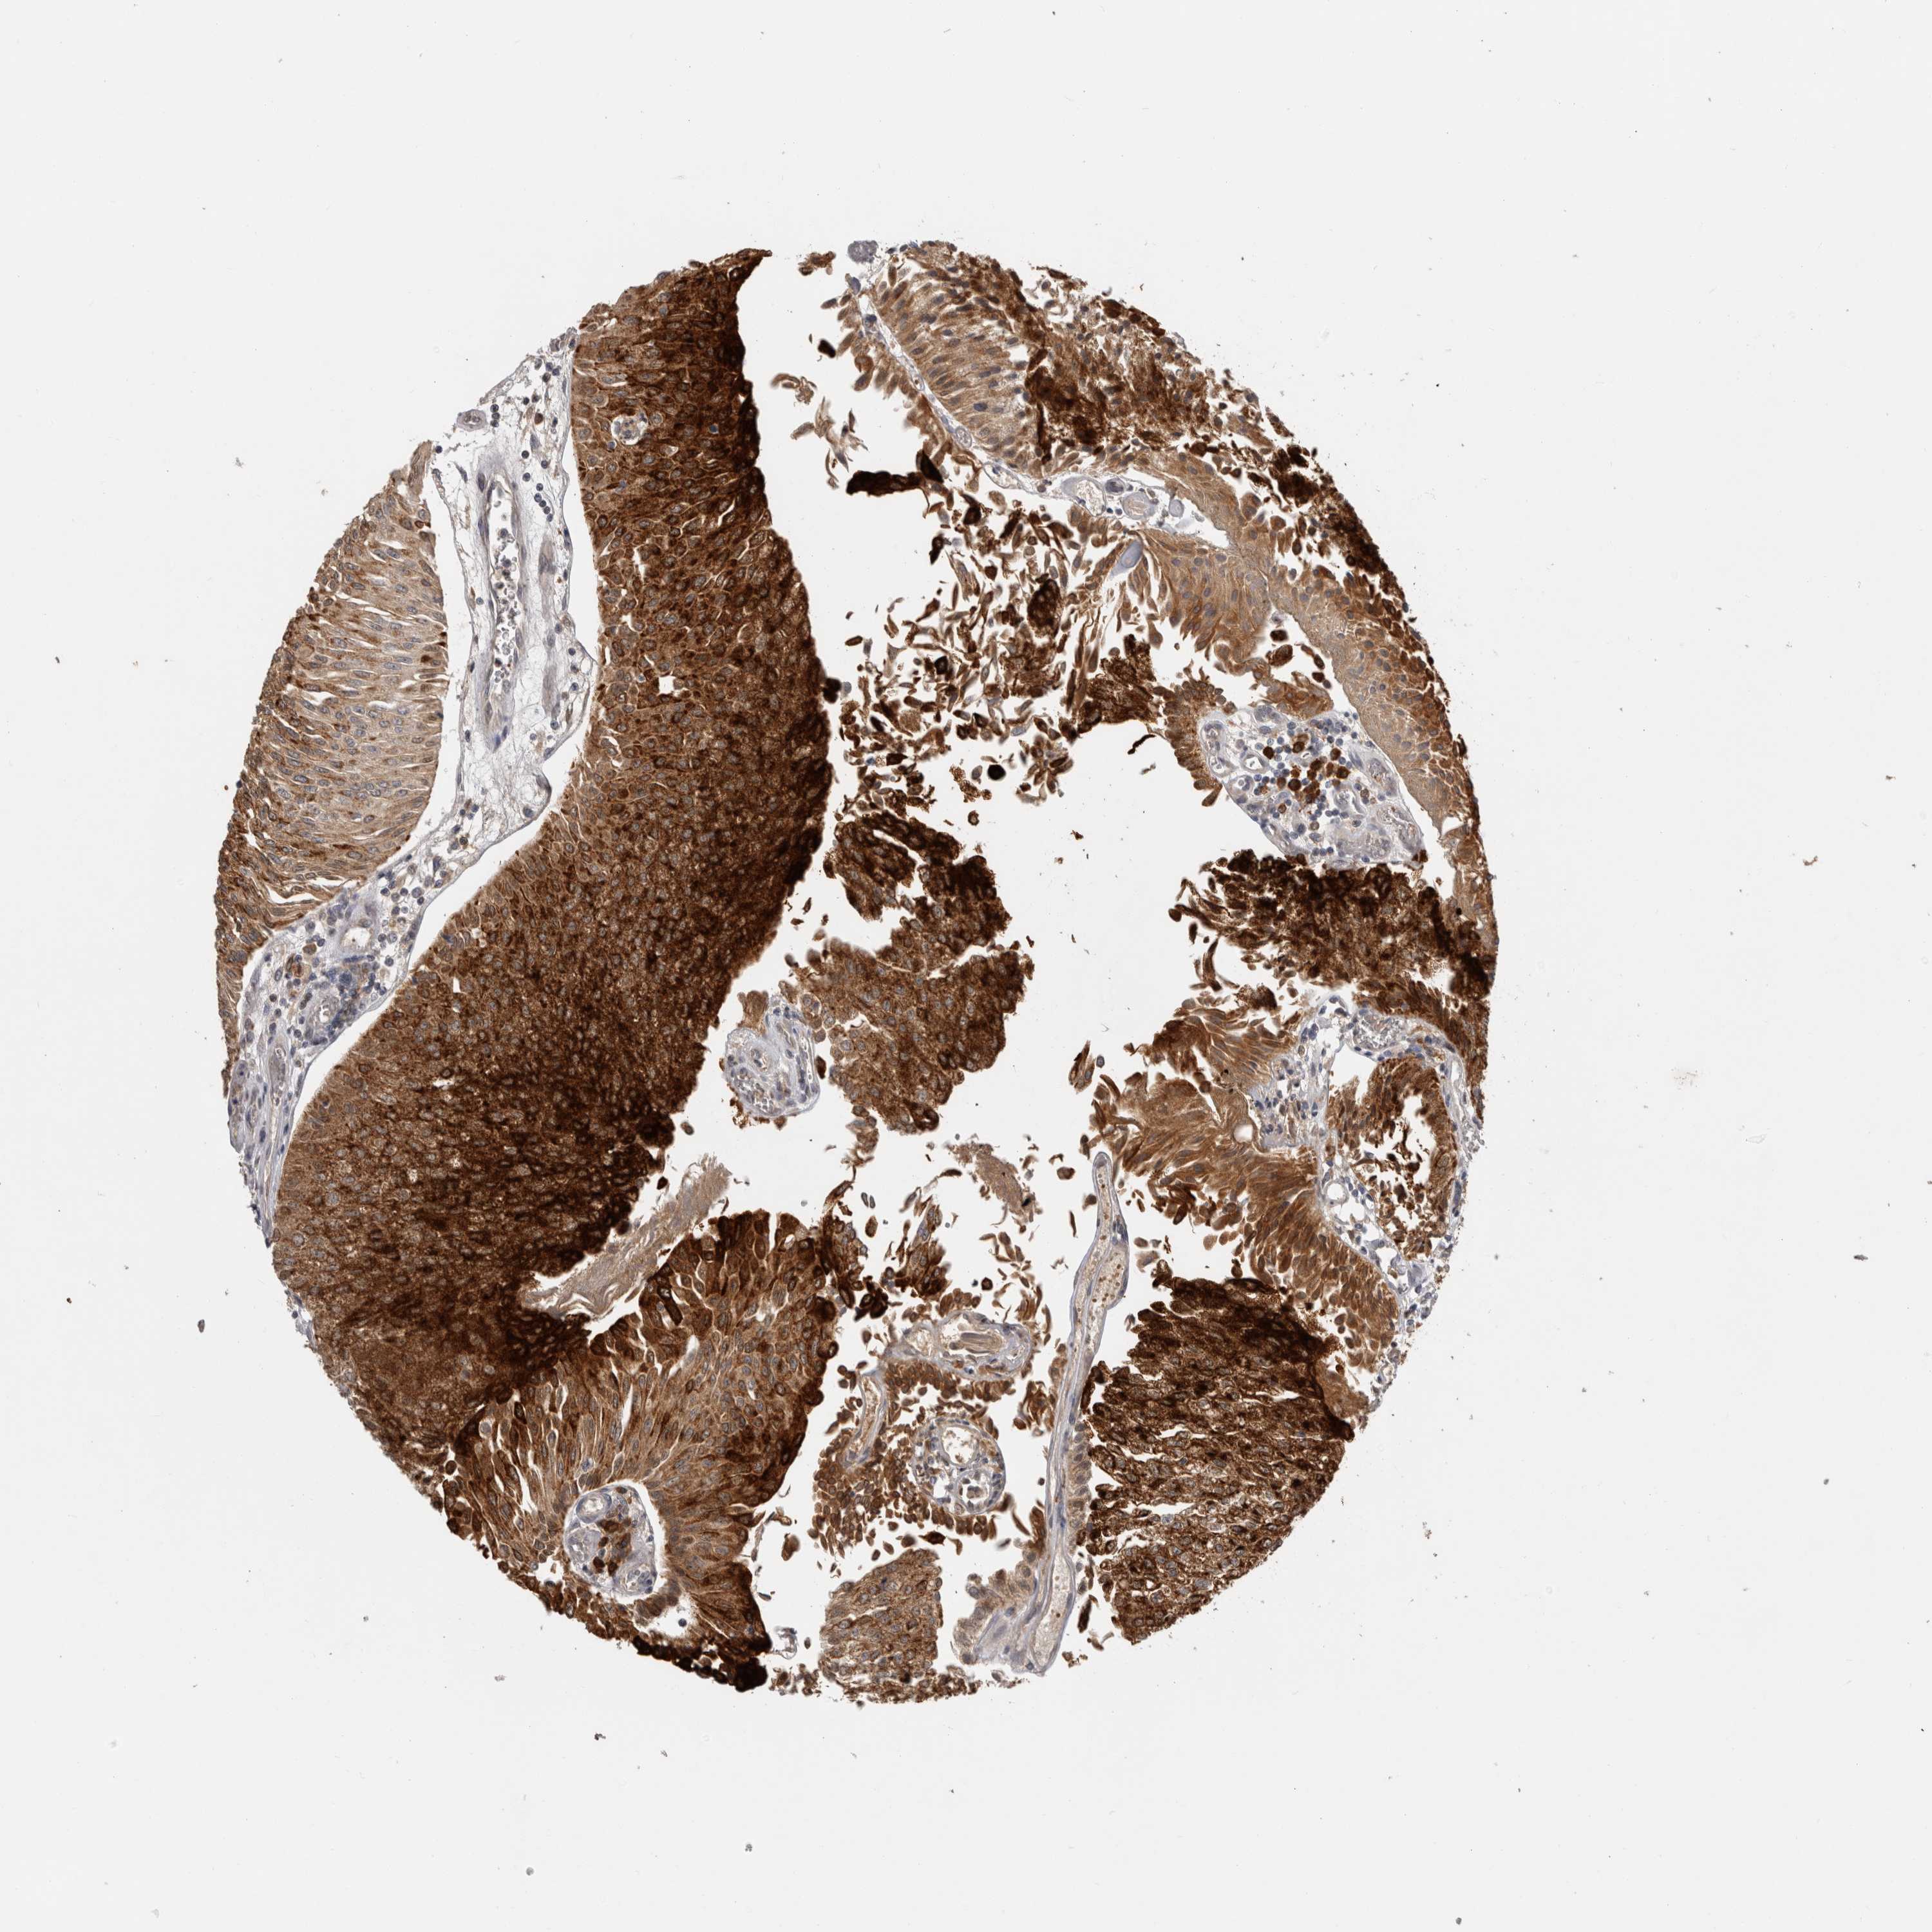

UROTHELIAL CANCER - Protein expressioni

A mouse-over function shows sample information and annotation data. Click on an image to view it in a full screen mode. Samples can be filtered based on level of antibody staining by selecting one or several of the following categories: high, medium, low and not detected. The assay and annotation is described here.

Note that samples used for immunohistochemistry by the Human Protein Atlas do not correspond to samples in the TCGA dataset.

Antibody stainingi

Antibody staining in the annotated cell types in the current human tissue is reported as not detected, low, medium, or high, based on conventional immunohistochemistry profiling in selected tissues. This score is based on the combination of the staining intensity and fraction of stained cells.

Each image is clickable and will lead to virtual microscopy that enables deeper exploration of all samples and also displays staining intensity scores, fraction scores and subcellular localization as well as patient and tissue information for each sample.

Antibody HPA001078

Antibody CAB026695

Staining

High

Medium

Low

Not detected

Intensity

Strong

Moderate

Weak

Negative

Quantity

>75%

75%-25%

<25%

None

Location

Nuclear

Cytoplasmic/membranous

Cytoplasmic/membranous,nuclear

Urothelial carcinoma, High grade

Urothelial carcinoma, Low grade

Adenocarcinoma, NOS